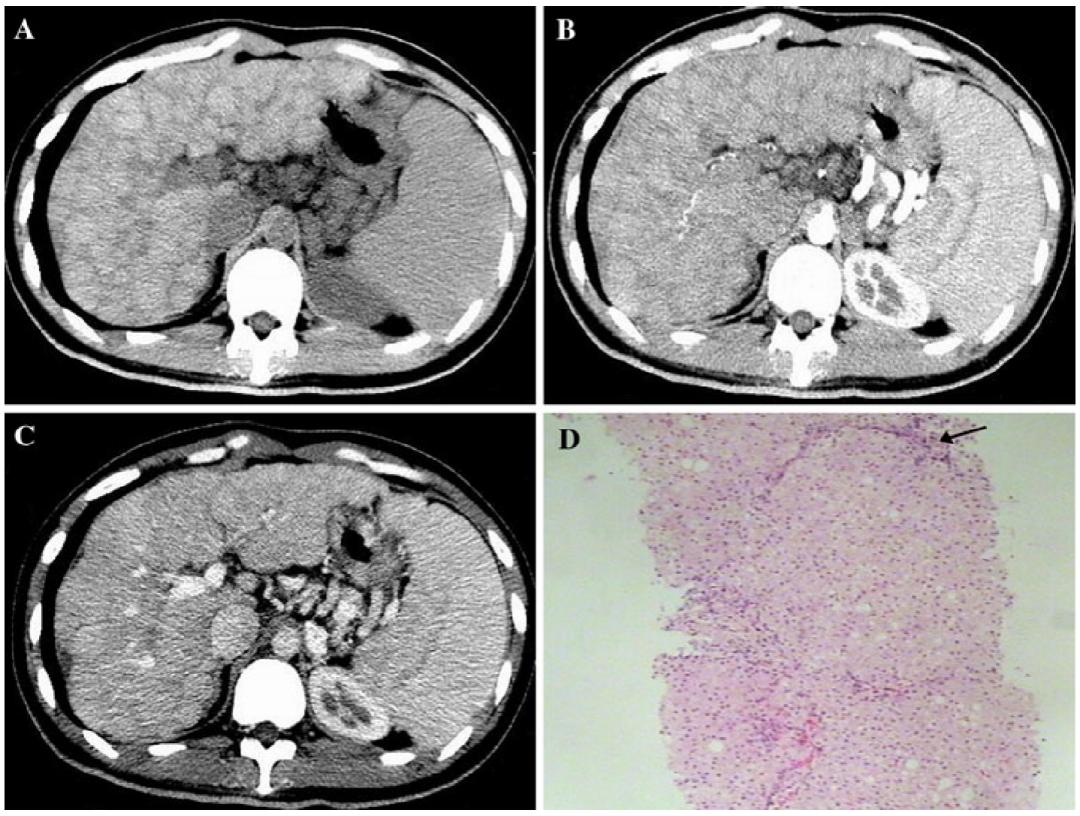

我们再来看第2个病例:46岁男性患者,因低血压、全身可凹性水肿、劳力性呼吸困难。行腹盆增强CT检查,检查图像如下:

我们再看一下肝脏层面增强CT图像(依次是平扫、动脉期、门脉期、延迟期):

患者的影像学,需要我们影像及临床大夫仔细考虑的就是:肝脏体积增大、密度弥漫性增高。

回到本文中的第2个病例:46岁男性患者,因低血压、全身可凹性水肿、劳力性呼吸困难就诊。

经询问病史:

(1)7年前:多饮、多食、多尿;皮肤色素沉着;双下肢水肿;

(2)4年前:自觉肝大(肋下可及);

(3)近一个月:低血压、全身可凹性水肿、劳力性呼吸困难。

患者血常规:WBC 6.29×109/L,NEUT# 4.18×109/L,Hb 145g/L,PLT 95×109/L(正常);

生化检查:ALT 122U/L,ALP 138U/L,AST 145U/L(升高);

铁四项:Fe 190.8μg/dl,TRF 1.40g/L,,TIBC 192μg/dl,IS 99.3%,TS 96.6%,Fer 5793ng/ml(升高);

心肌酶谱:cTnI 0.091μg/L,NT-proBNP 1600pg/ml(升高);

超声心动图:心肌病变;全心增大;轻-中度二尖瓣关闭不全;三尖瓣关闭不全;左右室收缩功能重度减低;左室限制性舒张功能减低。

结合影像学及实验室辅助检查可确诊:该患者是血色病患者。

患者没有做心肌MRI,基因分析等检查,无法明确鉴别是原发性还是继发血色病,但一些典型特征:皮肤特征性发黑、无外源内源铁的异常沉积病史、CT显示脾脏密度正常、超声提示心肌病变,血检正常、心肌酶谱NT-proBNP异常,可以推断很大可能属于原发性血色病。